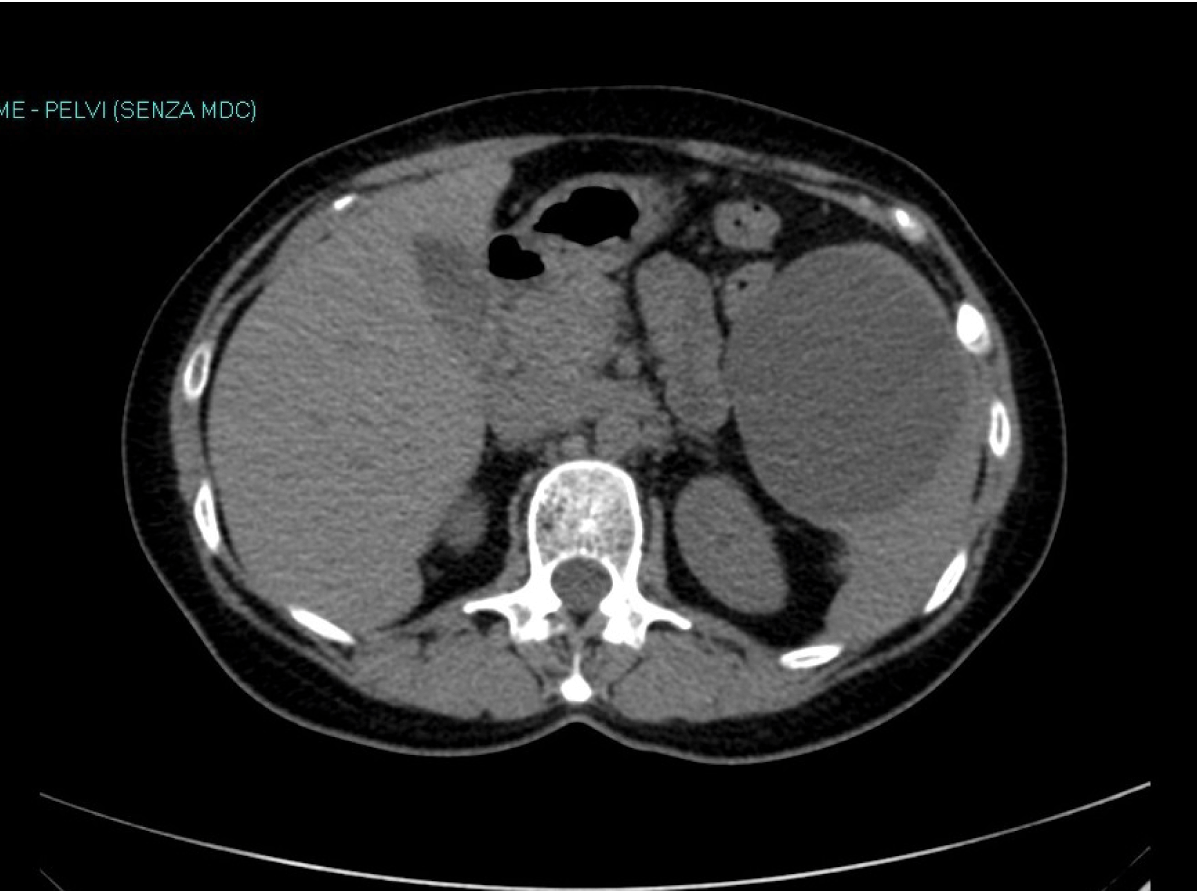

For this reason we agreed to adopt a wait-and-see strategy. She was monitored for 24 hours in the surgical ward, than discharged. Pain subsided gradually in a week or so. Three months later, a repeat CT scan (Figure 2) revealed that the cyst had completely disappeared. Now, more than 2 years after that episode of pain, the patient is completely fine and asymptomatic. A recent ultrasound scan confirmed the absence of any splenic cyst.

Figure 2: Computed tomography scan three months later showing complete resolution of the cyst.